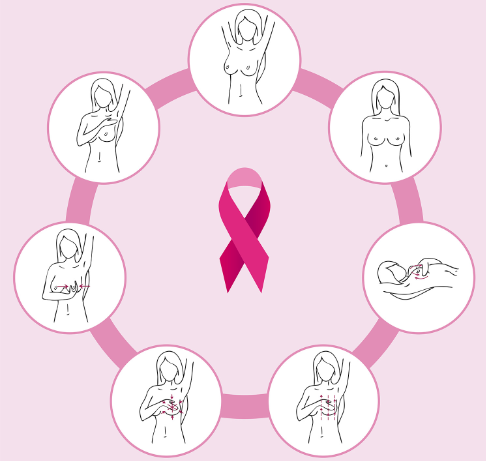

Samopregled dojki

Zajedno sa periodičnim specijalističkim pregledima i laboratorijskim analizama, samopregled značajno umanjuje rizik od pojave i širenja karcinoma grudi.

- Od navršene 20. godine života

- Makar jednom mesečno